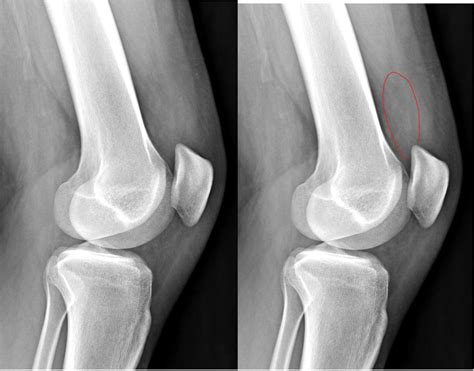

Discover effective knee effusion treatment options to reduce swelling and alleviate joint pain. Learn about proven relief strategies, including rest, physical therapy, aspiration, and medication, to manage excess fluid buildup. Understand the underlying causes of a swollen knee and explore expert recovery tips to restore mobility, improve comfort, and get you back on your feet quickly.